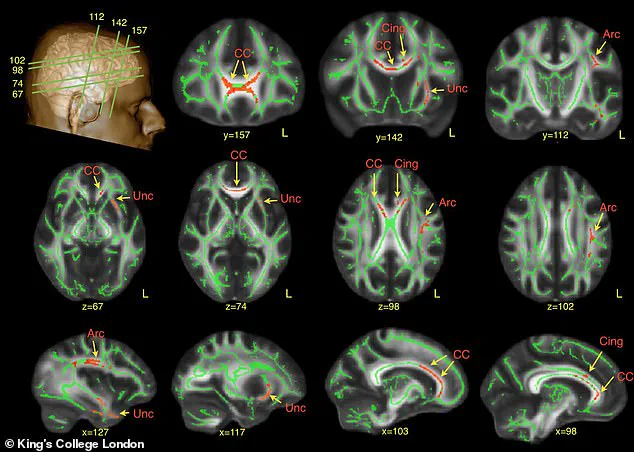

This could involve advanced neuroimaging techniques, behavioral assessments, and collaboration between veterinarians and human neuroscientists.

Further analysis has revealed that dogs with this genetic mutation also experience disruptions in neural communication.

Studies have shown that these dogs exhibit lower levels of signaling between neurons in brain regions responsible for attention and social engagement.

This reduced neural activity correlates with diminished 'neural coupling'—a phenomenon where brain activity in interacting individuals synchronizes during social exchanges.

In human interactions, this synchronization is a hallmark of successful communication, but dogs with Shank3 mutations show significantly less alignment with human brain patterns during social encounters.